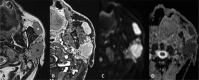

Inflammatory and obstructive disorders of the salivary glands are caused by very different pathological conditions affecting the gland tissue and/or the excretory system. The clinical setting is essential to address the appropriate diagnostic imaging work-up. According to history and physical examination, four main clinical scenarios can be recognised: (1) acute generalised swelling of major salivary glands; (2) acute swelling of a single major salivary gland; (3) chronic generalised swelling of major salivary glands, associated or not with "dry mouth"; (4) chronic or prolonged swelling of a single major salivary gland. The algorithm for imaging salivary glands depends on the scenario with which the patient presents to the clinician. Imaging is essential to confirm clinical diagnosis, define the extent of the disease and identify complications. Imaging techniques include ultrasound (US), computed tomography (CT) and magnetic resonance (MR) with MR sialography.